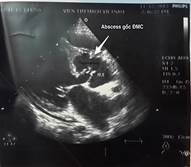

Kết quả siêu âm tim qua thành ngực cho thấy hình ảnh sùi van động mạch chủ, áp xe thành trước động mạch chủ lan tới 1/3 trên vách liên thất gây hở chủ nhiều. Sùi van hai lá gây hở hai lá nhiều và giãn các buồng tim (Hình 1,2). Điện tim đồ cho thấy block nhĩ thất cấp 3 (Hình 3). Cấy máu cấp ở 3 vị trí khác nhau cho kết quả âm tính. Bệnh nhân được hội chẩn nội – ngoại khoa và được chỉ định phẫu thuật cấp cứu.

| Hình 1,2: Hình ảnh abscess gốc ĐMC và vách liên thất trên siêu âm tim. | |